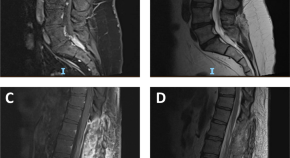

Spinal cord ischaemia is a rare complication following the gluteal injection of Benzathine benzylpenicillin. The hypothesis is embolization of the Penicillin products retrogradely through the Superior gluteal artery and cause occlusion of the vasculature that supply the spinal cord. This article includes literature review of the hypothesis behind the Spinal cord ischaemia and highlights the previous cases reported.